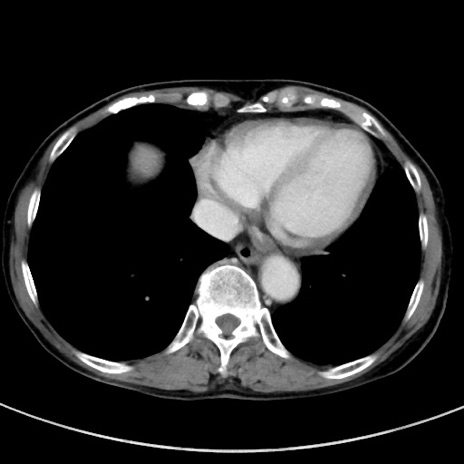

症例23(横断像)

【症例】70歳代女性

【主訴】下腹部痛・嘔吐

【現病歴】2日前より腹痛あり。昨日嘔吐あり。症状改善しないため来院。

【既往歴】胃GISTに対して胃部分切除後。

【身体所見】BT 37.1℃、BP 128/77mmHg、腹部:平坦・軟、下腹部に圧痛あり。

【データ】WBC 10200、CRP 0.31